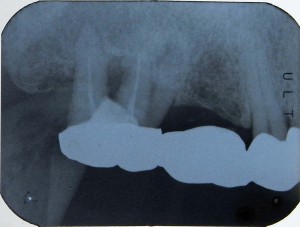

レントゲンで3股に分かれている股の部分の骨が溶けて、本来骨があれば白く映るのだが黒っぽく映っている

レントゲンで3股に分かれている股の部分の骨が溶けて、本来骨があれば白く映るのだが黒っぽく映っている